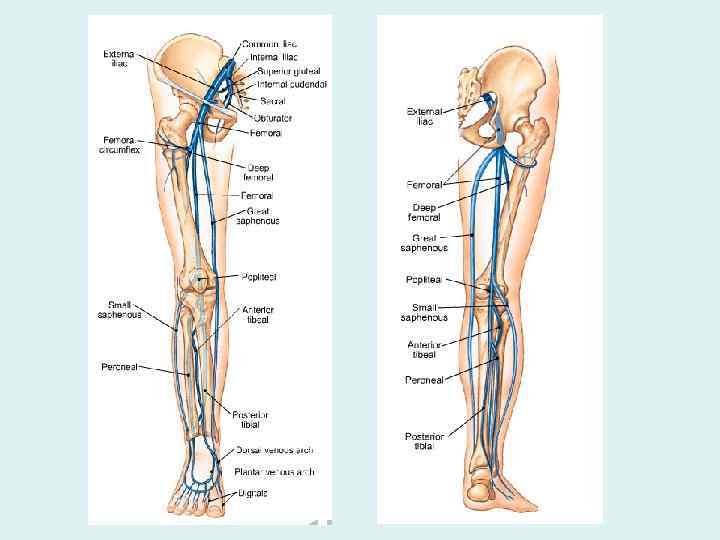

Вены нижней конечности • Глубокие вены • Поверхностные (подкожные)

Глубокие вены нижней конечности • Сопровождают одноименные артерии • Удвоены (кроме бедренной и подколенной) • Начинаются из тыльной (передние большеберцовые вены) и подошвенной (задние большеберцовые вены) дуг стопы

Поверхностные (подкожные) вены нижней конечности • Большая подкожная вена начинается от медиальной краевой вены тыла стопы, впадает в бедренную вену, сопровождает подкожный нерв • Малая подкожная вена начинается от латеральной краевой вены тыла стопы, впадает в подколенную вену, сопровождает икроножный нерв